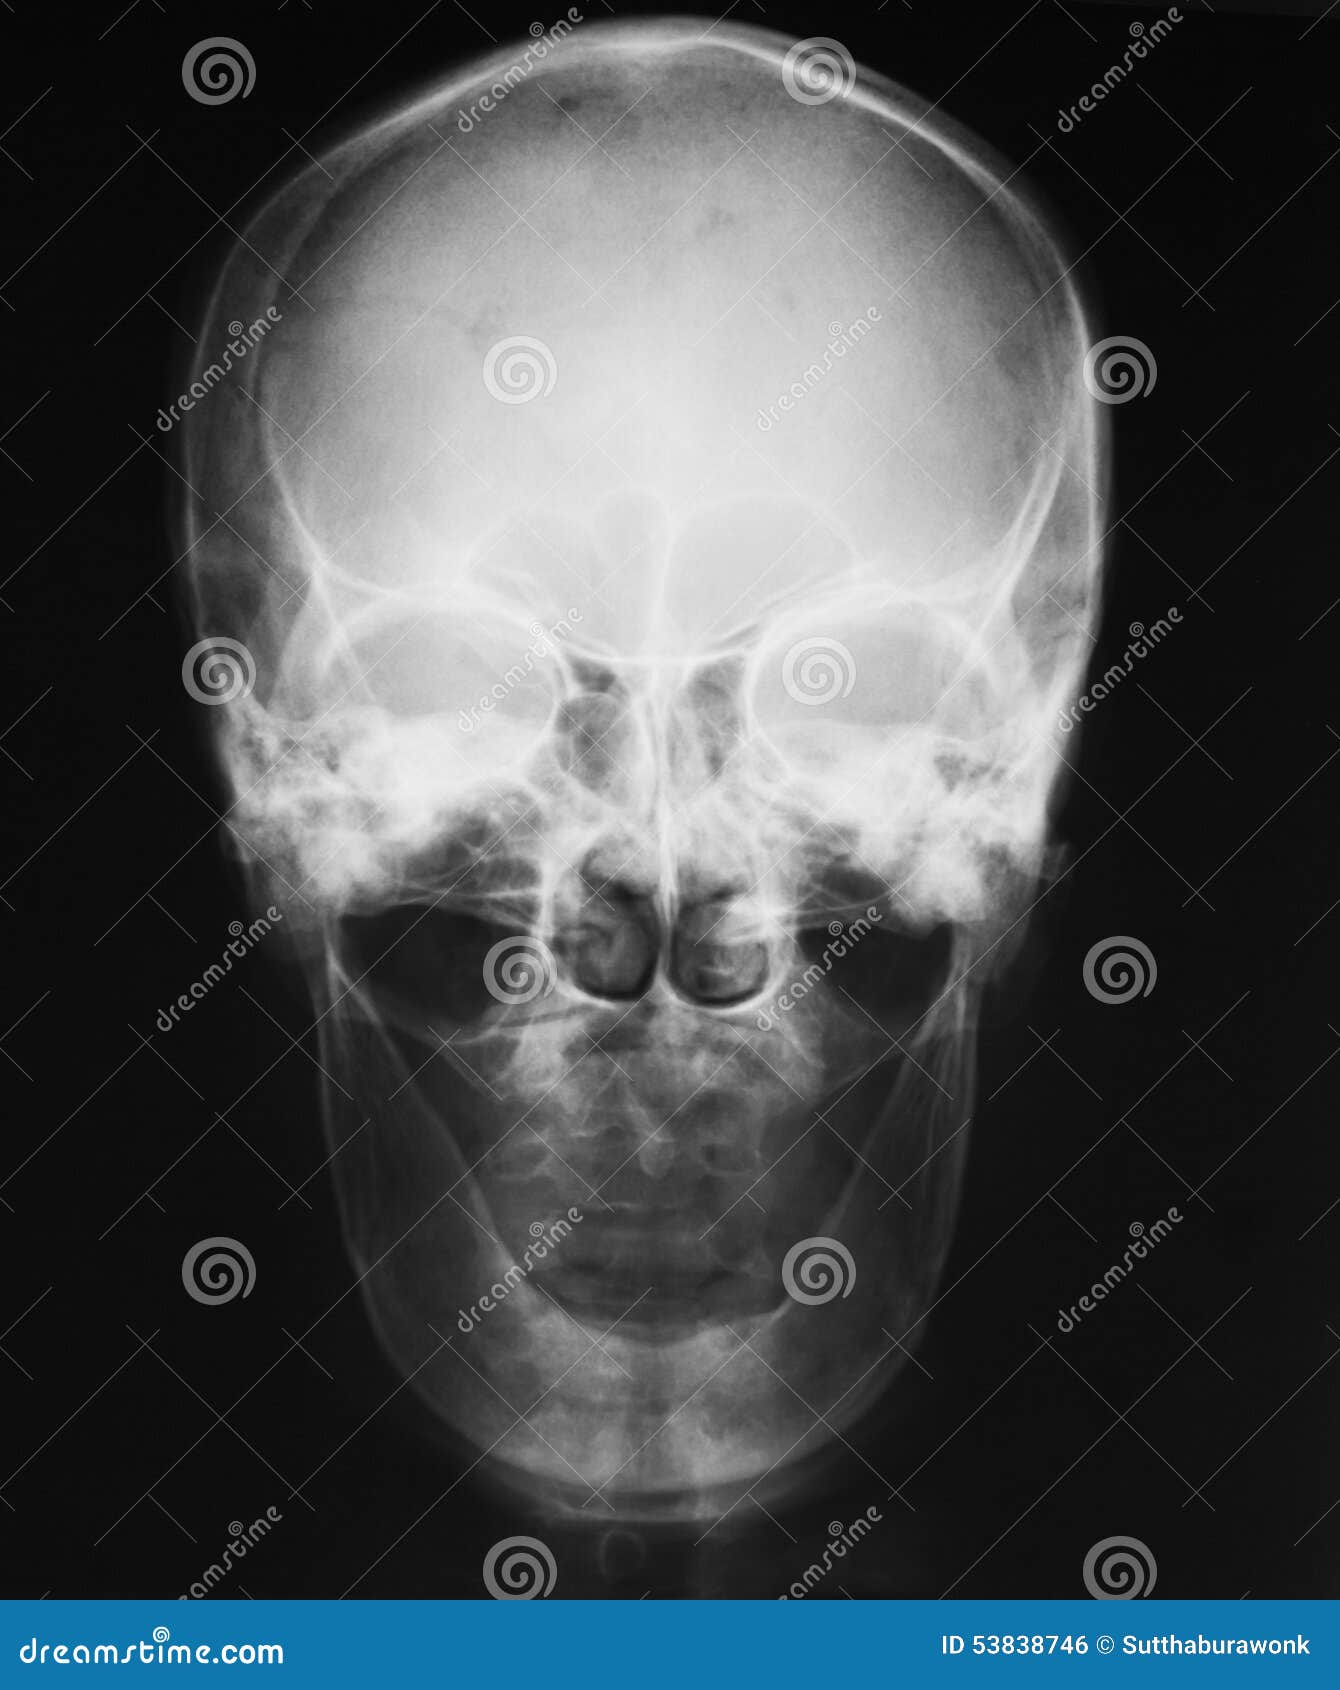

Mandible X Ray Ap . Change the scenario to a trauma patient in a cervical collar and it makes the most seasoned radiologic. 4 views • pa • towne • lateral obliques. Four sides of collimation closely collimate to mandible: This projection is useful in. It consists of a curved, horizontal portion, the body, and two. The mandible is the single midline bone of the lower jaw. The axiolateral oblique mandible view allows for visualization of the mandibular body, mandibular ramus, condylar process and mentum.